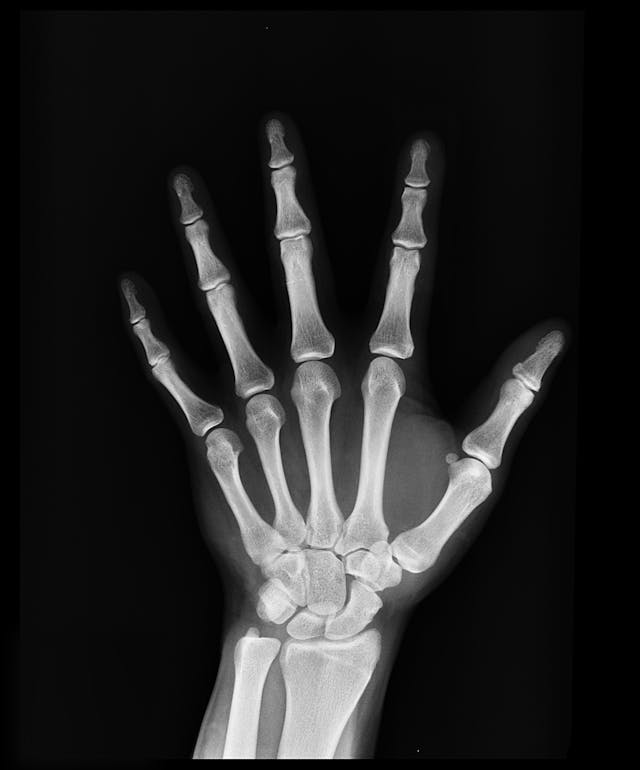

가벼운 충격이나 낙상에도 골절이 발생할 수 있습니다. 특히 손목, 척추, 고관절 부위가 흔한 골절 부위입니다.

골다공증은 주로 **이중에너지 X선 흡수법(DXA)**를 통해 진단합니다. 이 검사는 뼈의 밀도를 측정하여 정상, 골감소증, 골다공증 여부를 판별합니다. 또한 혈액 검사와 소변 검사를 통해 칼슘, 비타민 D 등의 영양 상태를 확인할 수도 있습니다.